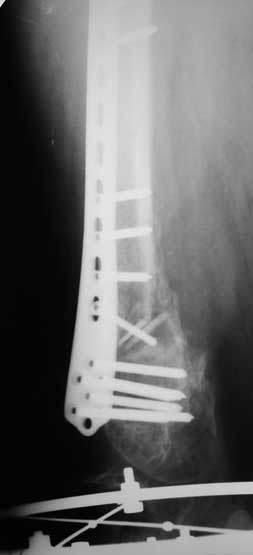

Уважаемые коллеги. Хотелось бы услышать Ваше мнение по следующему случаю. На лечении в отделении находится пациент 45 лет. С диагнозом: Замедленно консолидирующийся надмыщелковый перелом левой бедренной кости фиксированный пластиной от 06.12.10. Ложный сустав большеберцовой кости левой голени фиксированный АНФ от 06.12.10.

Анамнез: травма 18.06.10 в результате ДТП, водитель. Диагноз: Сочетанная травма головы, конечностей. ЗЧМТ. Сотрясение головного мозга. Открытый многооскольчатый внутрисуставной перелом мыщелков и нижней трети левой бедренной кости со смещением отломков. Открытый перелом костей левой голени в верхней трети со смещением отломков. Обширные рвано – ушибленные раны левого бедра, верхней трети левой голени. Находился на лечении в нескольких стационарах, где проводились оперативные вмешательства.

7. 06.12.2010г. Открытая репозиция, остеосинтез чрезмыщеково – надмыщелкого перелома левой бедренной кости пластиной со свободной костной пластикой из гребня левой подвздошной кости (во время операции из за сомнений в жизнеспособности костного отломка перелома бедра произведено его удаление. За счет чего образовался дефект костной ткани и укорочение левого бедра на 5,0 см; Мыщелки бедра были в сгибание, 5 месяцев нога не опорная, при попытке их репонировать крошились , зафиксировали как стояли. Остеосинтез переломов костей левой голени в АНФ.

Местно: Ходит при помощи костылей с попыткой полной нагрузки на левую ногу. Левый коленный сустав в положении разгибания. Движения в коленном суставе качательные. Воспалительных явлений области послеоперационных рубцов, мест выхода спиц нет. Анализы крови без воспалительной реакции.

Голень: выполнить остеосинтез левой большеберцовой кости интрамедуллярным стержнем с рассверливанием. На основании боковой рентгенограммы коленного сустава мыщелки бедра в сгибании, голень в переднем подвывихе, создается впечатление, что удастся завести стержень при такой контрактуре, или выполнить отсечение бугристости, попытаться согнуть колено и заштифтовать. Есть ли опыт штифтования при стойких контрактурах?

Бедро, коленный сустав: через 1 месяц срединным доступом с отсечение бугристости большеберцовой кости произвести реостеосинтез надмыщелкого перелома бедра с выведением мыщелков из сгибания. Коленный сустав: мобилизация головок четырехглавой мышцы бедра, артролиз, редрессация. Вопрос: на таком сроке – получиться ли одномоментно вывести мыщелки из сгибания или необходимы аппаратные способы устранения положения мыщелков?